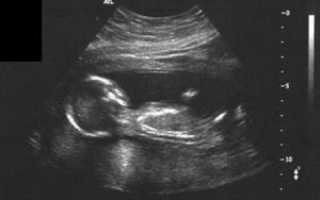

УЗИ на 17 неделе беременности уже может показать пол ребенка, если он повернется к датчику тем самым местом. Однако врача будут волновать другие показатели: размеры малыша и матки и их соответствие сроку, сердцебиение плода, его двигательная активность, состояние маточного миометрия, околоплодных вод, отсутствие грубых аномальных нарушений и так далее.

УЗИ показывает наличие сердцебиения у малыша. На экране монитора вино плодное пустое яйцо, или уменьшенные размеры эмбриона.

По данным УЗИ размеры эмбриона меньше положенного срока беременности. Сердцебиение у него отсутствует.

При УЗИ также можно выявить анэмбрионию — разновидность неразвивающей беременности, когда плодное яйцо пустое, без эмбриона.